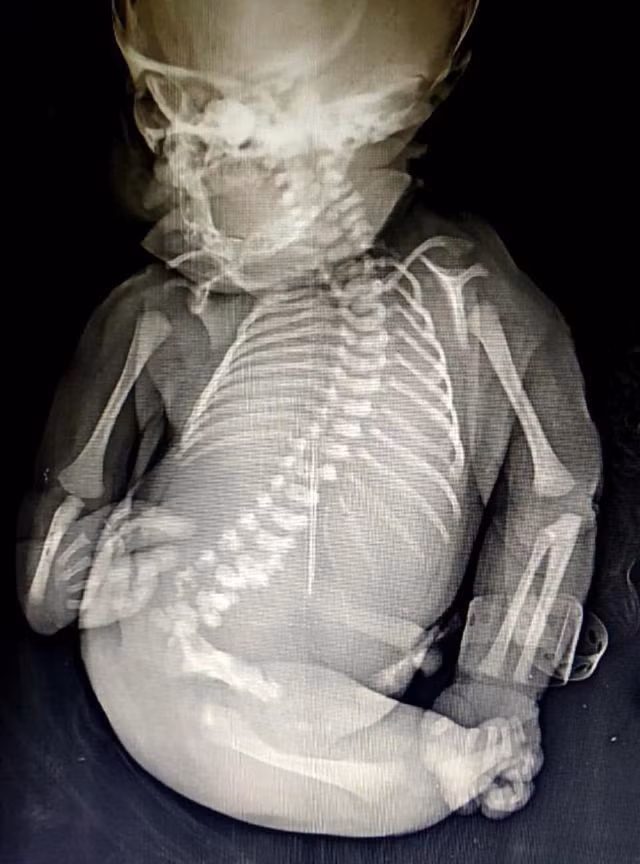

Disksha Kamble 25 tuổi đã vô cùng choáng váng khi sinh ra đứa bé có hai chân dính liền trông như đuôi cá. Hội chứng người cá hay còn gọi sirenomelia là một hội chứng bẩm sinh vô cùng hiếm gặp gây ra những bất thường ở cột sống và chân. Trẻ mắc hội chứng này sẽ chào đời với một phần hoặc toàn bộ chân hợp nhất.

“Đó là một tình trạng cực kỳ hiếm hoi. Người mẹ đã đến lúc 7 giờ sáng và khoảng 9 giờ sáng, đứa trẻ chào đời theo phương pháp tự nhiên. Chúng tôi dự định đón phần đầu rồi chân nhưng một cái đuôi cá lại xuất hiện. Tất cả đều bị sốc khi thấy đứa trẻ. Các sinh viên của tôi chưa bao giờ thấy điều như thế trước đây. Em bé không chỉ có phần chân hợp nhất, thiếu bộ phận sinh dục mà còn có những dị thường bên trong như dị dạng về thận và phổi. Đứa trẻ không thể sống quá 15 phút”, tiến sĩ Sanjay Bansode, bác sĩ phụ khoa tại bệnh viện cho biết.